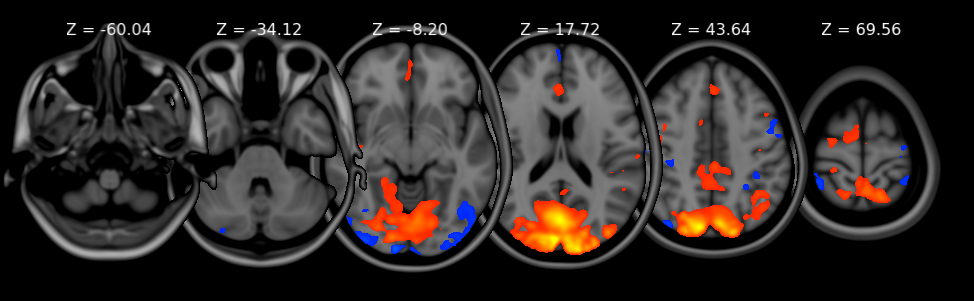

Orthographic/lightbox views

FSLeyes 1.19.0.dev10+gc3a33e578 has two primary 2D views - the orthographic (ortho) view, and the lightbox view.

Ortho view

The ortho view comprises three canvases, which display your overlays along three orthogonal planes. For a NIFTI image which is oriented acording to the MNI152 template, these canvases correspond to the sagittal, coronal, and axial planes.